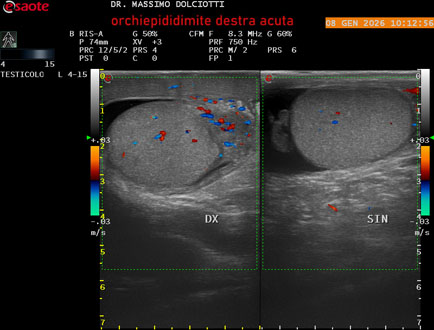

Data inserimento: 08/01/2026

Ecografia del: 08/01/2026

Strumento: Esaote MyLab Eight

Sonda: Lineare Multifrequenza 4-15 MHz

Età Paziente: M 74 anni

Motivazione dell'esame: da 3 giorni dolore e tumefazione al testicolo destro.

Commento all'esame: le immagini ed il video documentano il didimo destro, aumentato di volume, con incremento della vascolarizzazione; aumentato di volume e di vascolarizzazione anche l'epididimo destro, Normale il didimo sin e l'epididimo sinistro, Gli elementi ecografici segnalati orientano per orchiepididimite destra acuta.

Conclusioni: orchiepididimite destra acuta (right acute orchiepididymitis).

Presentazione: Dr. Massimo Dolciotti - Ancona

Elaborazione digitale: Andrea Dini - Ancona